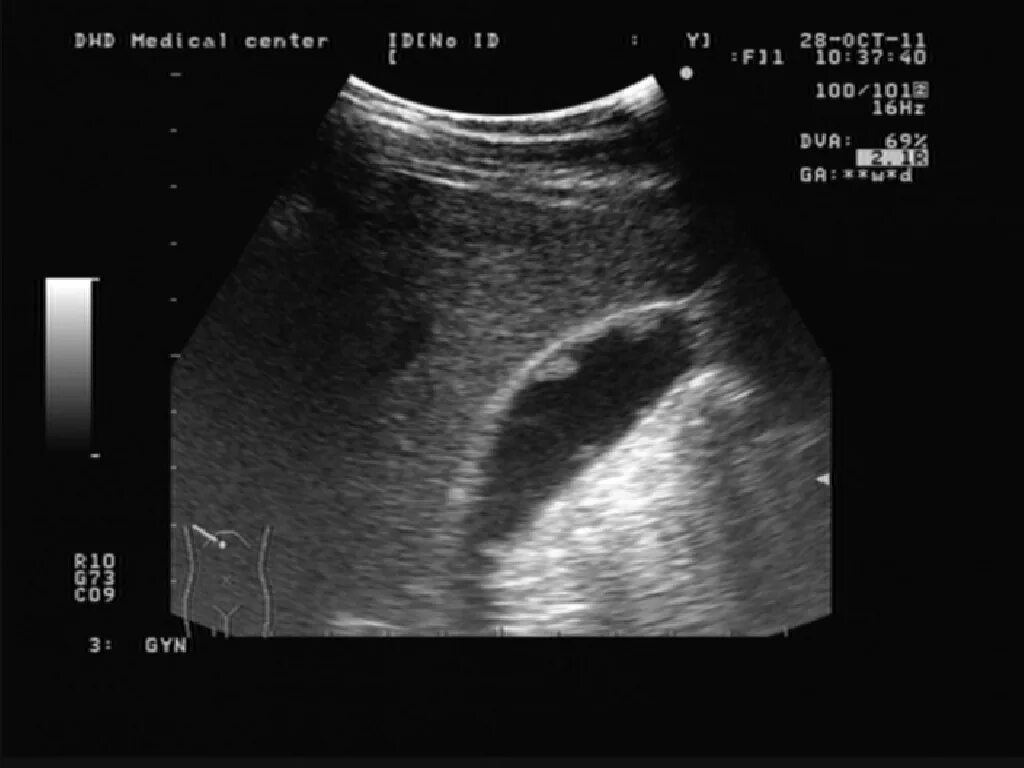

Какие полипы желчного пузыря